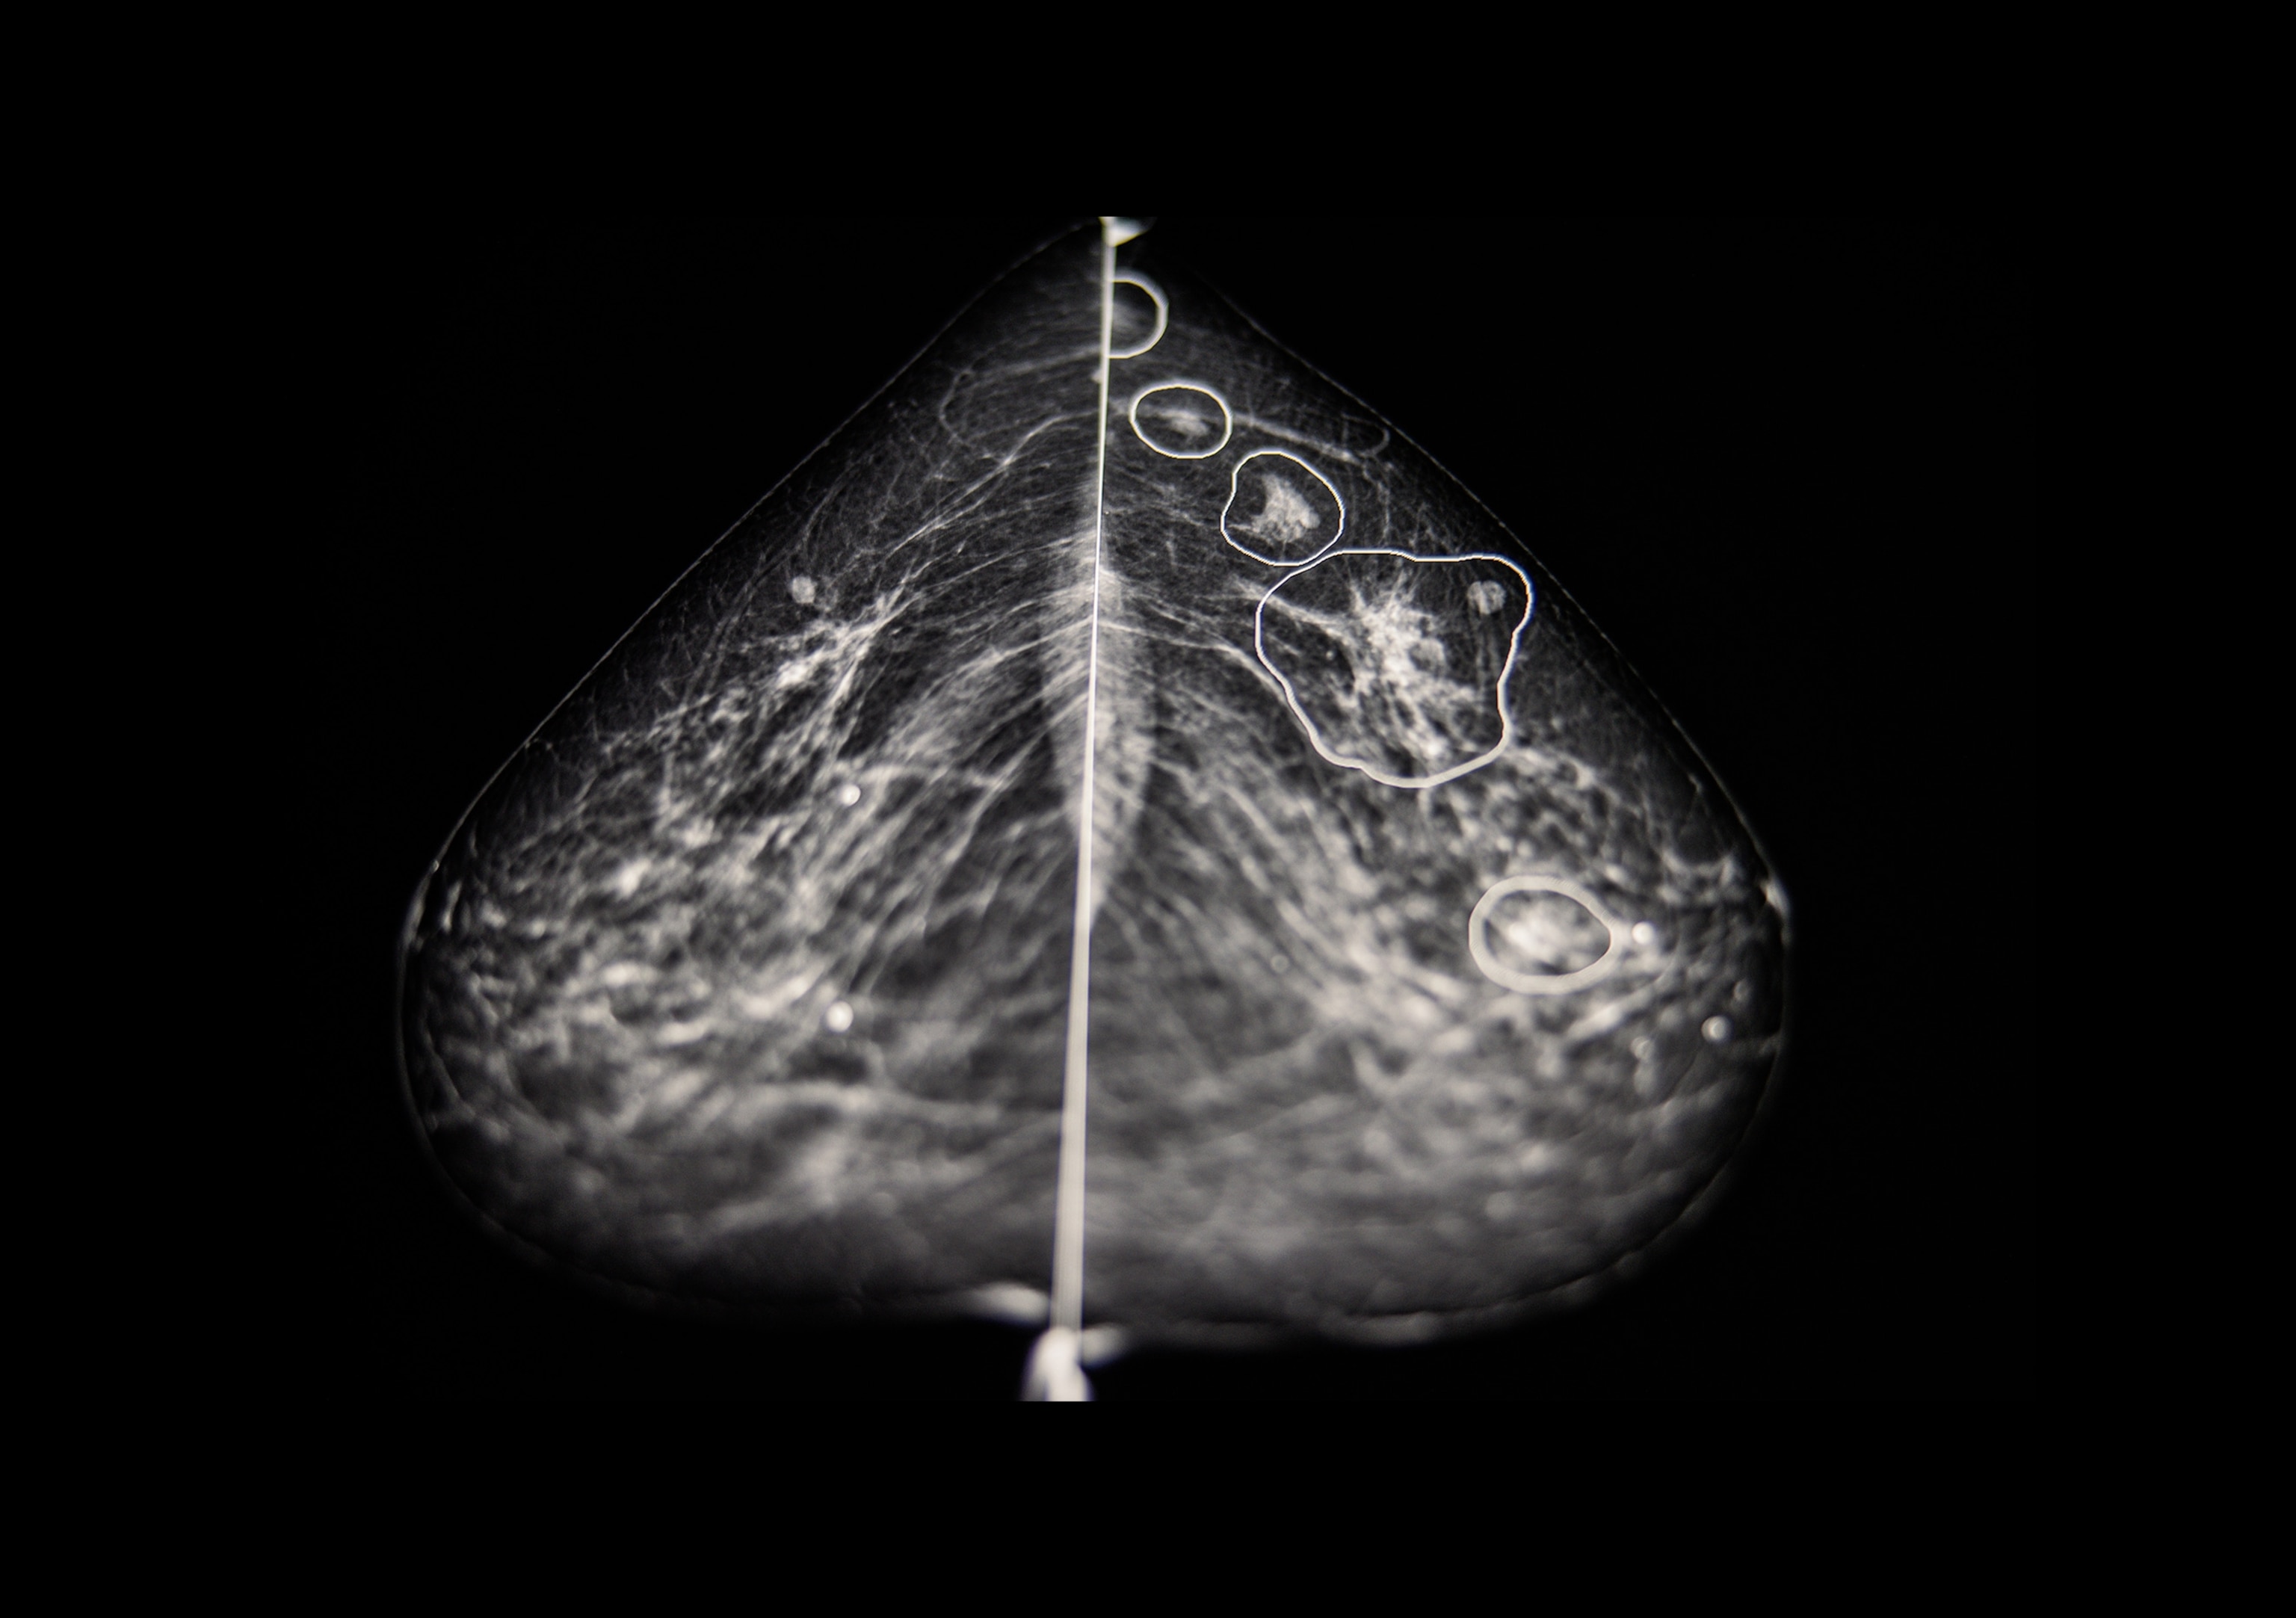

Now, there are clear guidelines for intensive screening (a.k.a., enhanced surveillance), often involving more frequent breast exams by a medical professional and mammograms plus breast MRI for women with a positive result. The goal is to try to detect cancer in the earliest stages if it does occur.